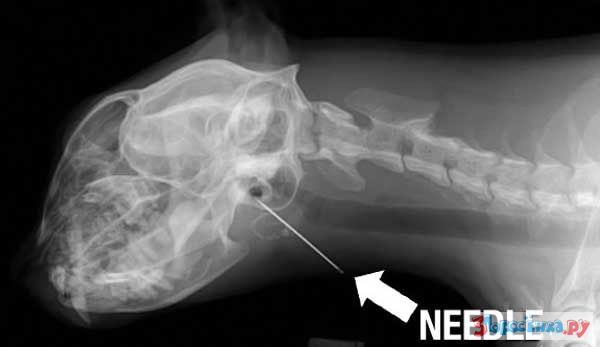

Нет ничего не перевариваемого

Некоторые собаки видимо полагают что их желудок способен переварить все на свете.